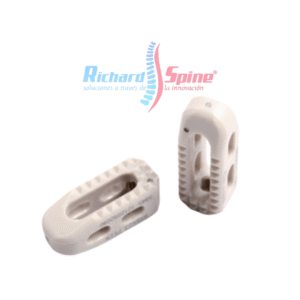

Caja de Fusión Intercorporal Cervical Anterior

- Implante de jaula de fusión intersomática cervical anterior